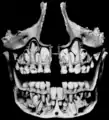

دندان نیش در انسان

۴ عدد دندان نیش در انسان وجود دارد که دو عدد آن در قوس فکی بالا و دو عدد دیگر در قوس فکی پایین قرار دارند. دندانهای نیش در دو طرف دندانهای پیش قرار دارند و اندازه آنها از اندازه دندانهای پیش بزرگتر است. ریشه این دندانها در داخل استخوان فک قرار دارد و به صورت برجستگی از روی لثه قابل مشاهده هستند.